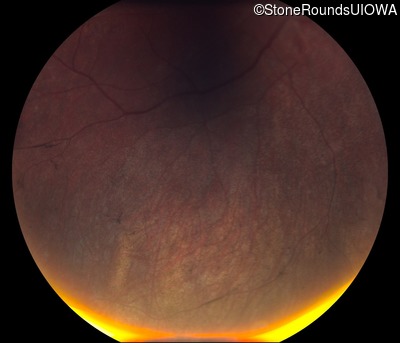

Fundus Photography - Right - No Light Perception

Exemplar